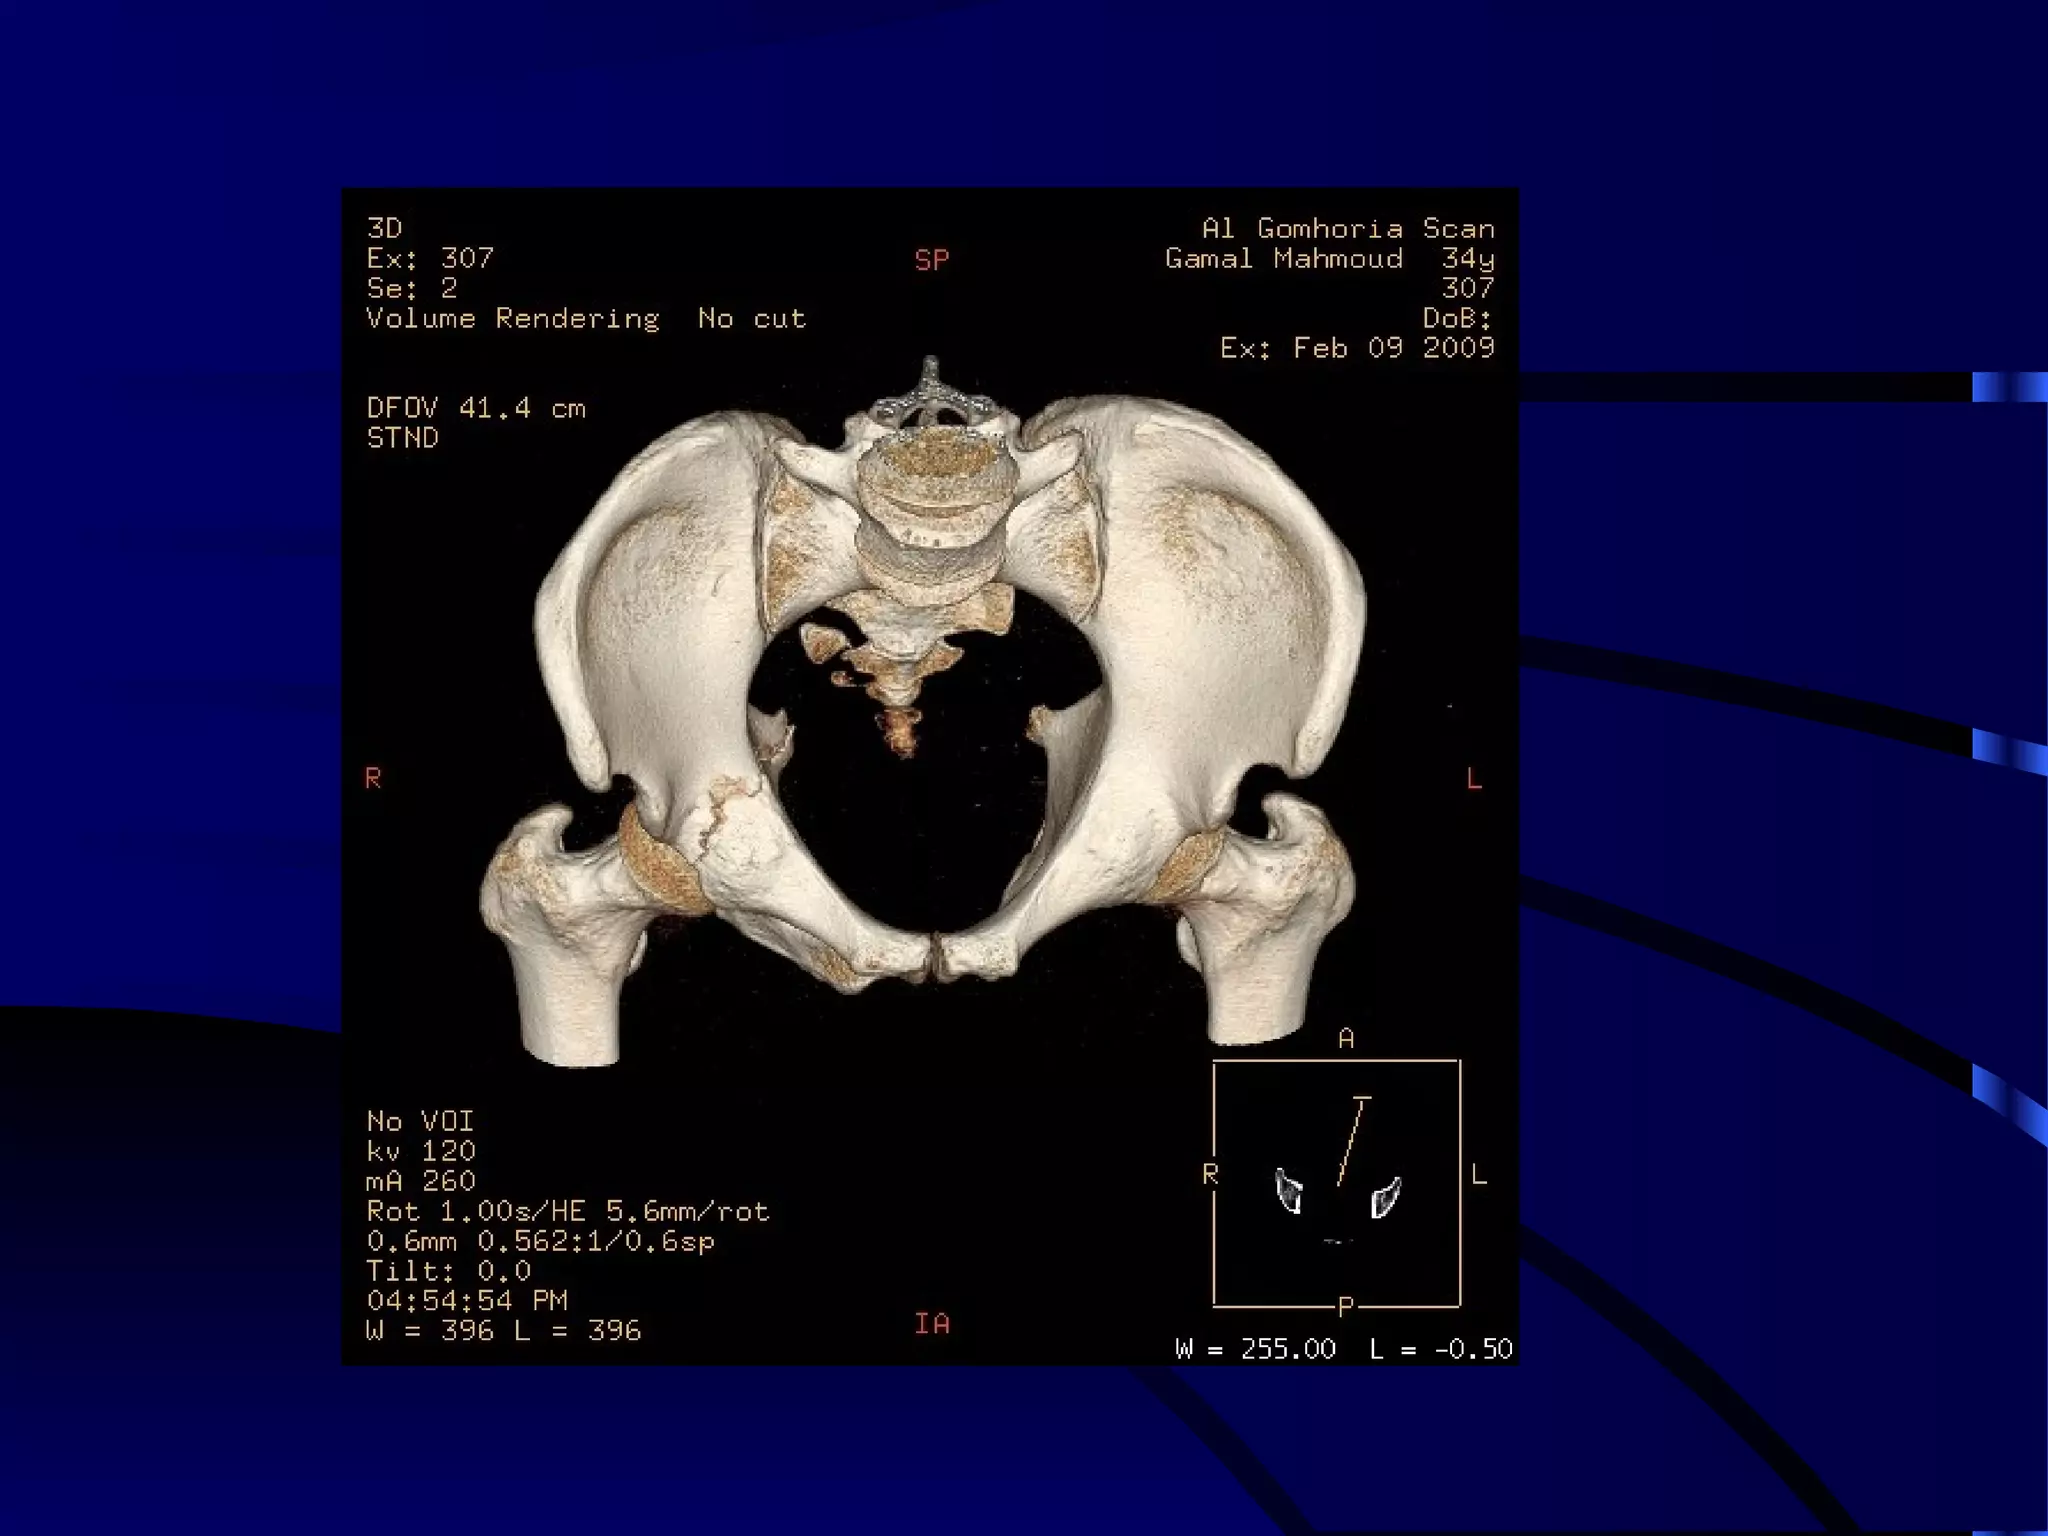

FRACTURE L.S.S.

FRACTURE PELVIS